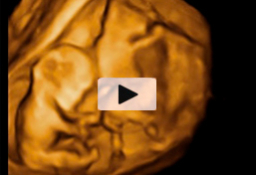

Eco 4D de gemelos de 12 semanas

Ecografía en 4D de gemelos de 12 semanas "contrapeados" En este caso, el gemelo que "baila" es el que está en parte inferior de la imagen o cabeza abajo. Ecografía Embarazo 4D Semana 12 - ANOMALIAS CROMOSÓMICAS Ecografía Embarazo 2D y 3D Semana 12 - ANOMALIAS CROMOSÓMICAS